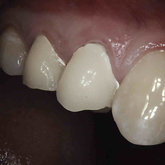

Porcelain crowns and restorations made in one appointment.

We make it a priority to incorporate the latest in dental technology in everything we do at our practice. ...